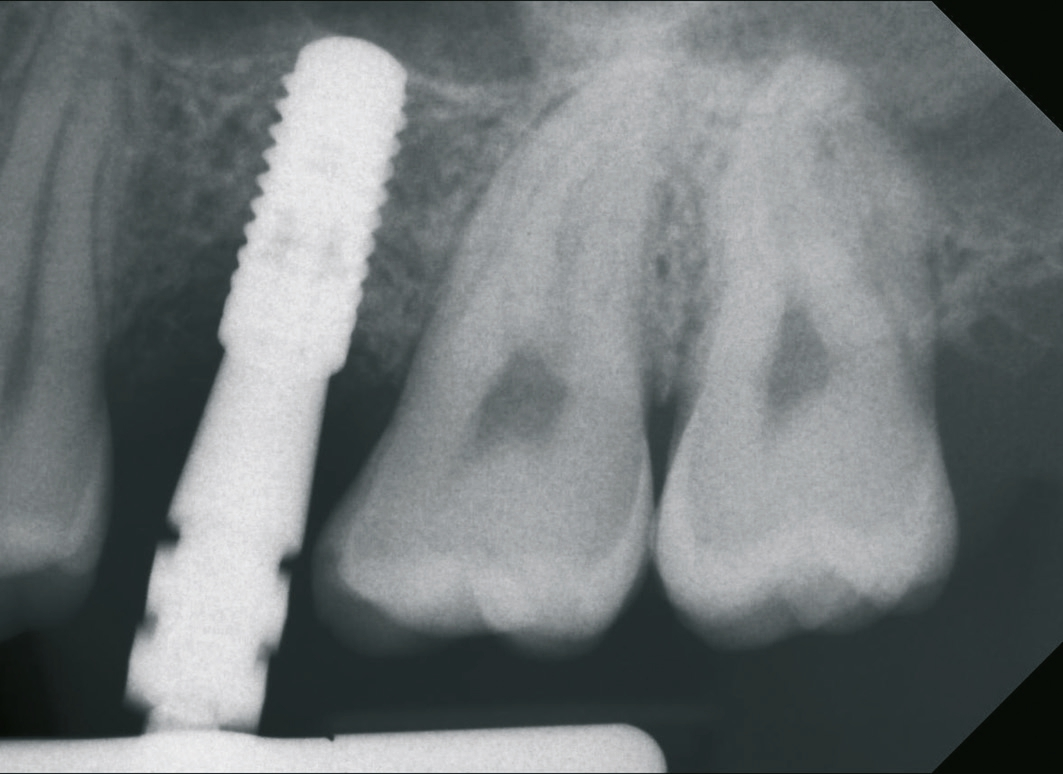

Ein 21-jähriger Patient stellte sich mit einer Perkussionsempfindlichkeit in regio 26 vor. Die klinische Untersuchung zeigte einen tiefzerstörten Zahn 26, dessen gesamte palatinale Wand tief fraktruiert war. Die Frakturgrenze verlief dabei weit unter dem palatinalen Zahnfleischrand (Abb. 1). Nach Erstellung eines Orthopantomogramms und einer radiologischen Einzelzahnbildaufnahme war eine längliche Verschattung am Apex der palatinalen Wurzel des Zahn 26 zu erkennen (Abb. 2), die den Verdacht einer überinstrumentierten Wurzelkanalaufbereitung der palatinalen Wurzel und einer Überstopfung des Füllmaterials bestätigte (Abb. 3). Nach konservierender Theapie wurde die Indikationsstellung für die Extraktion des Zahnes 26 mit einer Sofortimplantation gestellt. Der Periodontal-Screening-Index wies in allen Sextanten Grad 2 auf. Es folgte die Erstellung einer dreidimensionalen Röntgenaufnahme (Orthophos XG 3D, Dentsply Sirona, Bensheim) zur virtuellen Planung der Implantatposition. Die operative Planung erfolgte in der Planungssoftware coDiagnostiX 9.5 (dental wings, Montreal, Kanada) (Abb. 4).